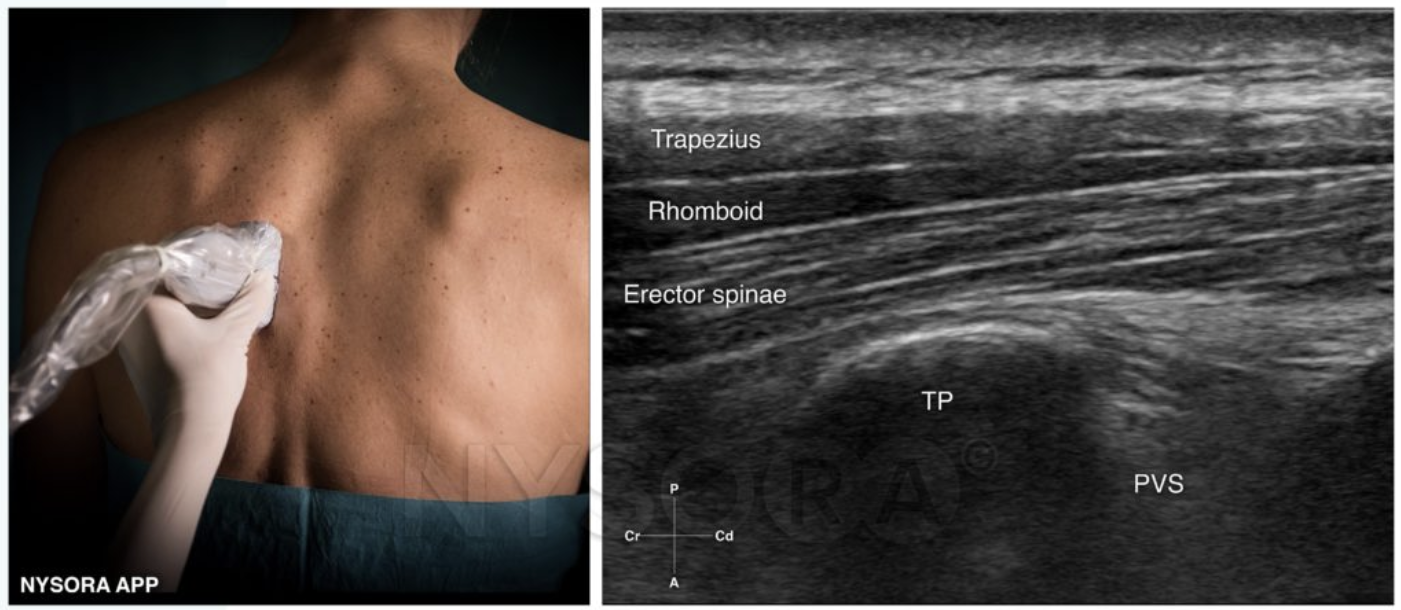

Describe the two commonly used ultrasound techniques

Transverse

- In plane technique

- US probe placed axially immediately lateral to midline

- Identify rib and move probe caudally to find intercostal space

- Visualise pleura and internal intercostal membrane

- This membrane is continuous with the superior costotransverse ligament

- Needle is advanced from lateral to medial towards the transverse process

- Visualise the pleura being pushed away